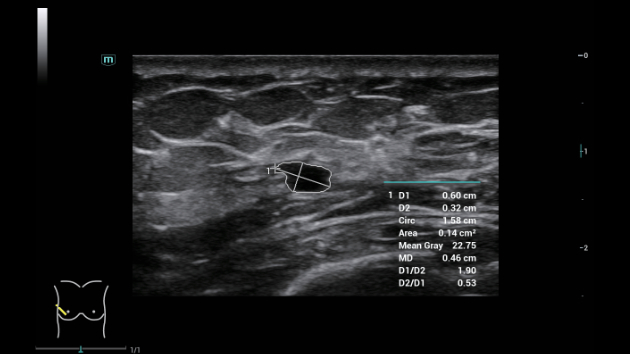

Soluzioni di diagnostica per immagini complete con tecnologia ZST+

La piattaforma ZST+ è un'innovazione straordinaria, che rappresenta un'evoluzione nel campo dell'ecografia. Grazie alla trasformazione delle metriche a ultrasuoni dal beamforming convenzionale all'elaborazione basata sui dati di canale, supera la tradizionale limitazione del trade-off tra risoluzione spaziale, risoluzione temporale e uniformità dei tessuti, offrendo una qualità d'immagine eccezionale per infinite soluzioni di imaging con miglioramenti continui.